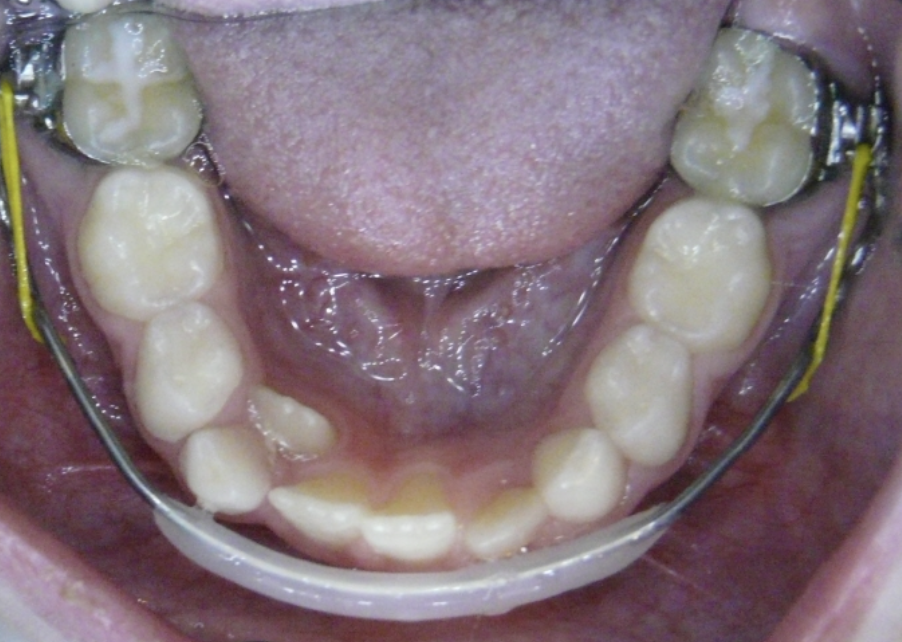

Crowding

Lack of space causes crowding as teeth erupt.